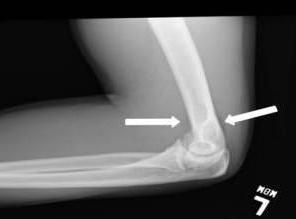

FOOSH (fall on outstretched hand) injury often results from slipping on ice, as well as skiing and snowboarding. Here a 27-year-old man presented a day after sustaining a FOOSH injury while roller skating. He complained of pain when pronating and supinating his left arm, but there were no limitations in range of motion. A lateral plain x-ray film shows an anterior and posterior fat pad sign on the left elbow. A second image of a posteroanterior view also revealed a slight hematoma positioned medially and just inferior to the radial head.